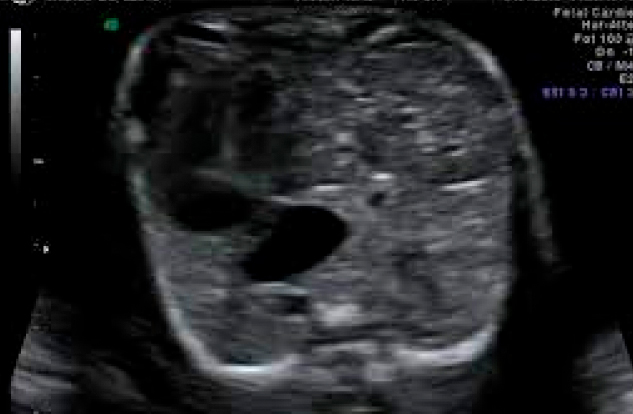

Al estar comunicados el tórax y el abdomen, las vísceras de este (intestino, estómago, bazo y en ocasiones el hígado) suben al tórax provocando una compresión de ambos pulmones que impide su adecuado crecimiento y maduración. Al nacimiento (momento en que el bebé utiliza por primera vez sus pulmones para respirar y adquirir oxígeno) los pulmones pueden ser tan pequeños en algunos casos que el bebé presente la muerte inmediata por asfixia e hipertensión pulmonar.

Su objetivo no es reparar el defecto del diafragma sino aumentar el desarrollo, crecimiento y maduración de los pulmones antes del nacimiento para mejorar las probabilidades de sobrevivir disminuyendo el riesgo de asfixia e hipertensión pulmonar al nacer.La cirugía es de mínima invasión y se realiza con anestesia local a la madre y anestesia intramuscular al feto. Se hace un corte menor de 5mm en el abdomen de la madre, se introduce un fetoscopio dentro del útero y bajo visión directa y sin realizar ningún corte al feto, se introduce el fetoscopio a través de la boca fetal hasta entrar a su tráquea donde se coloca y se infla un balón. Este se deja inflado en la tráquea del feto de 2 a 6 semanas para ser retirado antes de su nacimiento.